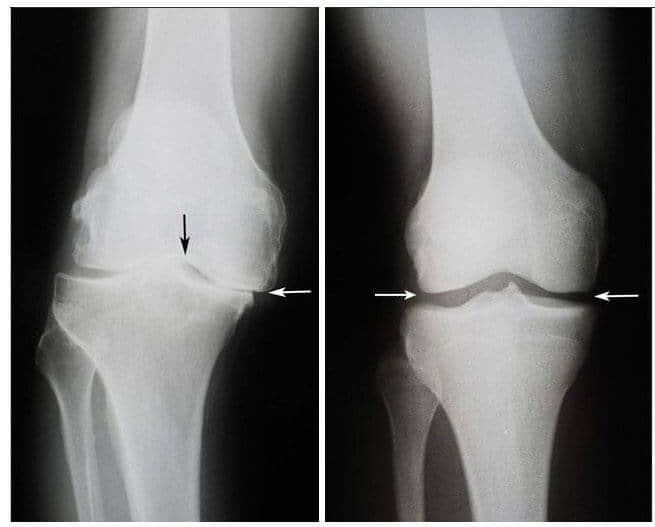

Одлево: рендгенската снимка на десното колено на Виолетова Јовановска, 75 години. Ткивото на 'рскавицата е речиси целосно уништено. Препорака на лекарите е зглобот да го замени со вештачки.

Оддесно: рендгенската снимка на десното колено на Виолета Јовановска после лекувањето со гелот Nautobone.